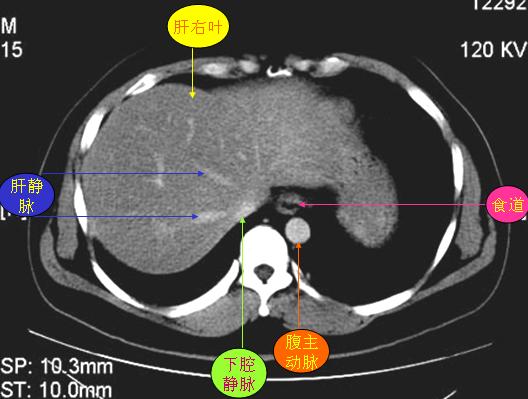

腹部ct解剖与基本病变